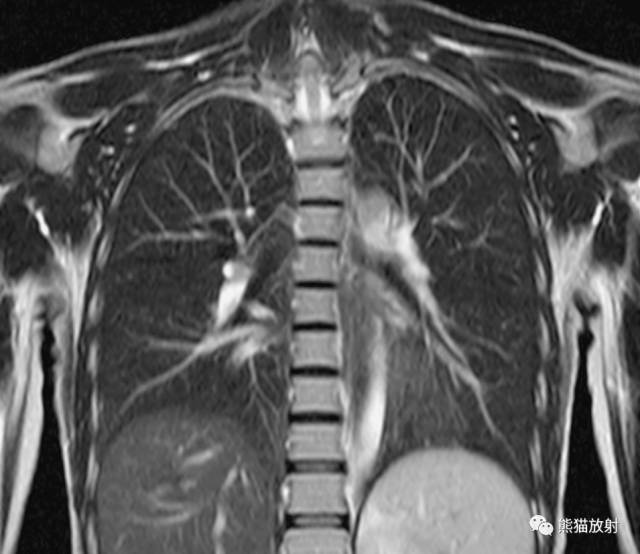

冠状断层肺段分布

上叶【S1:尖段、 S2:后段、 S3:前段】

中叶【S4:外段 、S5:内段】

下叶 【S6:背段、S7:内基底段、S8:前基底段、S9:外基底段、S10:后基底段】

左肺

上叶【S1+2:尖后段、S3:前段、S4:舌叶上段、S5:舌叶下段】

下叶【S6:背段、S7+8:前内基底段、S9:外基底段、S10:后基底段】